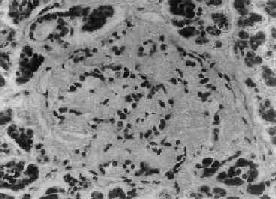

1.胰岛的病变不同类型的糖尿病及其不同时期,病变差异甚大。Ⅰ型糖尿病早期可见胰岛炎,胰岛内及其周围有大量淋巴细胞浸润,偶见嗜酸性粒细胞。胰岛细胞进行性破坏、消失,胰岛内A细胞相对增多,进而胰岛变小,数目也减少,有的胰岛纤维化;Ⅱ型糖尿病用常规方法检查时,早期几无变化,以后可见胰岛B细胞有所减少。常见变化为胰岛淀粉样变,在B细胞周围及毛细血管间有淀粉样物质沉着(图15-18),该物质可能是胰岛素B链的分解产物。

糖尿病之胰岛图示胰岛淀粉样变

图15-18 糖尿病之胰岛

图示胰岛淀粉样变